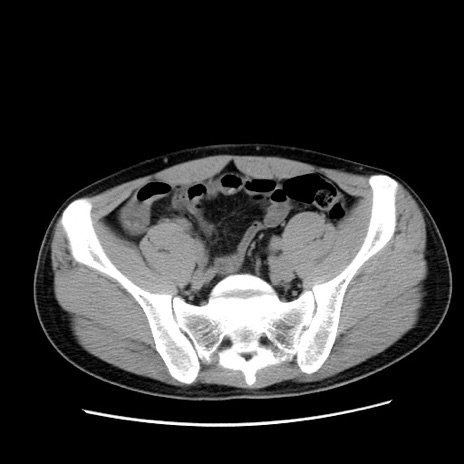

症例36(横断像)

【症例】20歳代 男性

【主訴】心窩部痛

【現病歴】今朝より上腹部痛あり。一旦軽快していたが再度出現したため救急要請。昨日夕に白身の魚を含む刺身を食べた。

【身体所見】BP 136/89mmHg、HR 74/min、BT 37.0℃、腹部:膨満、軟、心窩部に圧痛あり。反跳痛なし、筋性防御なし、腸雑音やや亢進あり。

【データ】WBC 17700、CRP 0.48